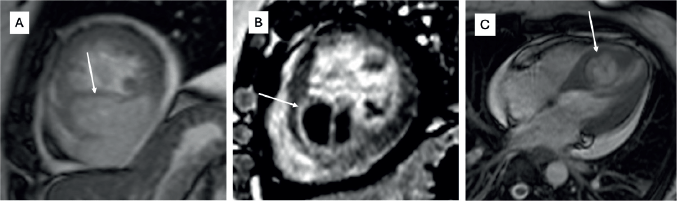

Figure 1. Cardiac MRI of a patient with synovial sarcoma of interventricular septum β (a): Bright blood (SSFP sequence) in short-axis view showing the heterogeneously hyperintense mass lesion (arrow) involving the septum and extending into the inferior wall of the left ventricle; (b): Late gadolinium enhancement (LGE) sequence in short axis view showing heterogenous peripheral enhancement with central non-enhancing component; (c): Bright blood (SSFP sequence) in four chamber view showing the mass (arrow) with cystic appearance within it.

Primary cardiac sarcomas are rare and the prognosis is not encouraging. It is a disease often seen in middle-aged patients with a slight male predominance. In our study, the median age was 33 years (range 17β53 years) and had male predominance. The most common site of primary lesion in a cardiac sarcoma is right atrium and most often angiosarcoma is found to be the cause, which is reflected in the present study as well. Siontis et al [7] stated that 46% patients present with metastatic disease upfront. In the present case series, 33.3% had a metastatic disease at presentation. Although literature shows that some cardiac sarcomas can initially be misdiagnosed as a benign cardiac pathology, the exact percentage is not clear. In our study, 50% of patients were misdiagnosed at presentation, which led to a median delay of 1.75 months losing precious time in treatment initiation and were found to have extensive disease/metastatic disease at the time of diagnosis. This highlights that cardiac sarcomas can have certain atypical features on imaging modalities like echocardiography or cardiac MRI and hence, definitive diagnosis should always be based on histopathology. In a developing country like ours, tubercular involvement of right heart is not very uncommon and hence right-sided angiosarcomas may be misdiagnosed as the same. Also, cystic appearance of sarcoma can sometimes defy the usual diagnostic features, like in one of our cases, where it masqueraded as a hydatid cyst (Figure 1) [20].